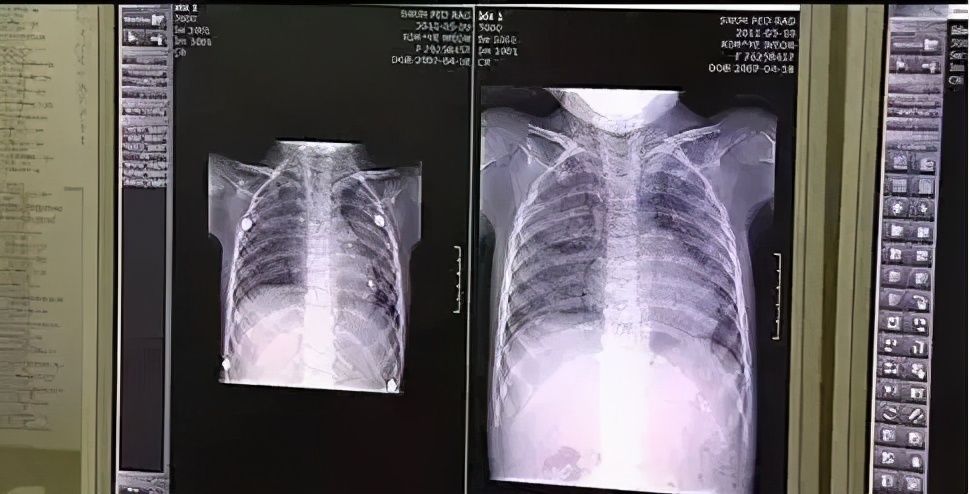

2011年,韩国发生了 多起 孕妇和宝宝因不明原因的急性肺病而去世 的情况 。

当时,韩国的检查机关着手调查,初步认定这是一种“类流行病”的急性肺病。

所以,那会他们的应对手段也是 参考“流行病”来防治的。 可是一系列的防治手段在这种“急性肺病”面前都没有效果,而因病死亡的病例也在不断持续……

一直到去年7月,【韩国社会灾难调查特别委员会】才公布了 爆发于2011年的“急性肺病事件”的调查结果——

加湿器杀菌剂中的聚六亚甲基胍盐酸盐(PHMG)成分,被认为是致死的元凶。

在调查中,他们发现患者有一个共性: 平均每年使用4个月左右的加湿器,每次加水时都添加杀菌剂PHMG,大概1个月就用掉1瓶杀菌剂。

但被加入加湿器被雾化后,PHMG成分就会进入人体的肺部,被人体吸收,进而 诱发支气管炎和肺泡损伤,导致不可逆的肺部纤维化,甚至死亡。

据统计, 当时的“加湿器杀人事件”直接造成67万人患病,1.4万人死亡!

而幸存下来的67万人, 有34.2万人患上鼻炎,20.3万人患上肺部疾病,16.6万人患上皮肤疾病,13.9万人患上哮喘,有些患者可能不幸患上多种疾病。